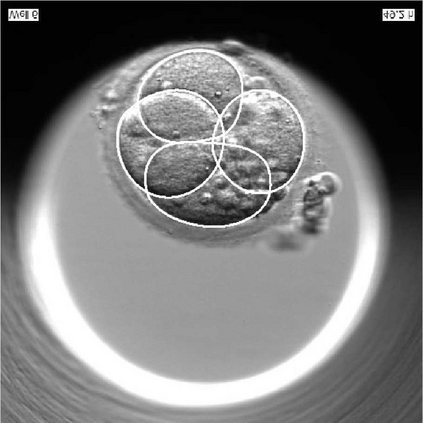

We present a novel method for identification of the boundary of embryonic cells (blastomeres) in Hoffman Modulation Contrast (HMC) microscopic images that are taken between day one to day three. Identification of boundaries of blastomeres is a challenging task, especially in the cases containing four or more cells. This is because these cells are bundled up tightly inside an embryo's membrane and any 2D image projection of such 3D embryo includes cell overlaps, occlusions, and projection ambiguities. Moreover, human embryos include fragmentation, which does not conform to any specific patterns or shape. Here we developed a model-based iterative approach, in which blastomeres are modeled as ellipses that conform to the local image features, such as edges and normals. In an iterative process, each image feature contributes only to one candidate and is removed upon being associated to a model candidate. We have tested the proposed algorithm on an image dataset comprising of 468 human embryos obtained from different sources. An overall Precision, Sensitivity and Overall Quality (OQ) of 92%, 88% and 83% are achieved.